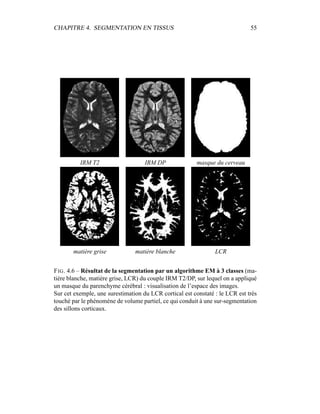

c’est donc sur elle que portera l’analyse lors de la segmentation en tissus et de la

présentation du modèle de volume partiel. Les autres modalités seront utilisées a

posteriori.

4.4 Segmentation en tissus.

4.4.1 Algorithme

Le but de cette segmentation en tissus sains est leur caractérisation, afin de

pouvoir construire un premier processus de détection des lésions de SEP. Même